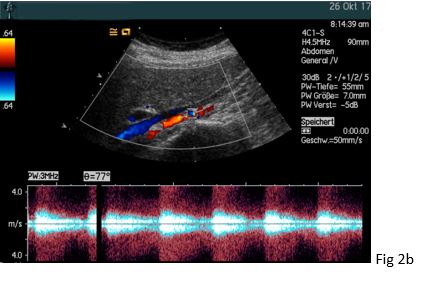

Figure 2: The retrocavally located right renal artery could be visualized posterior to the inferior vena cava (IVC) with a bruit in (a) and turbulent flow above 4 m/s in (b).